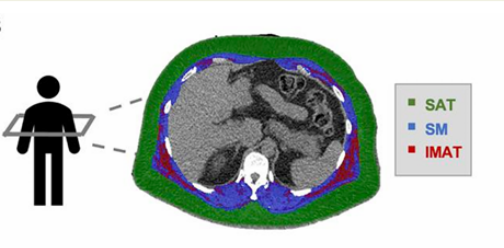

皮下脂肪组织(SAT)、骨骼肌(SM)和肌间脂肪组织(IMAT)通过第12胸椎水平CT检测(见下图)。

为了量化肌间脂肪量,研究者采用肌肉脂肪分数,即肌间脂肪组织/(骨骼肌+肌间脂肪组织)。